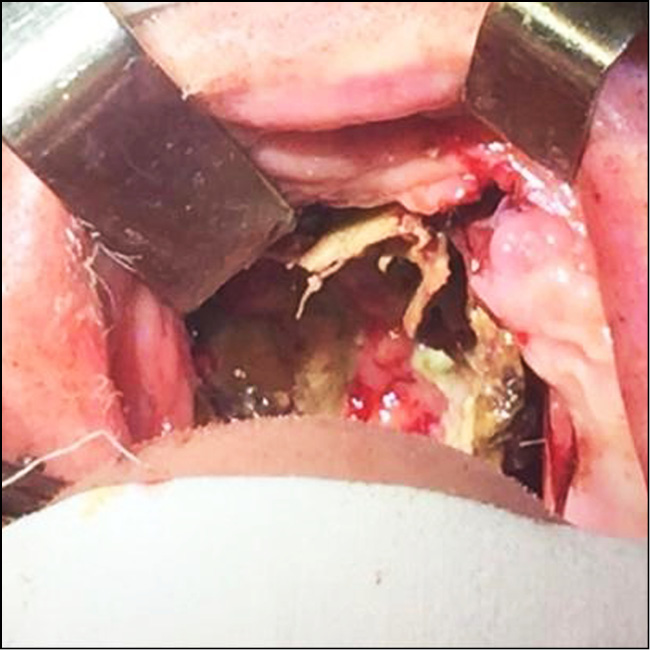

Объемная синусовая некрэктомия проводилась под контролем видеоэндоскопической визуализации. С помощью прямого эндоскопа 0° осматривалась полость носа и носоглотки. Зачастую визуализировались участки множественного некроза средних и задних отделов перегородки носа, задних концов нижних носовых раковин и средних носовых раковин, медиальной стенки верхнечелюстной пазухи с костной деструкцией на стороне поражения, некротизированные ткани в области решетчатого лабиринта и медиальной стенки орбиты. При этом противоположная сторона могла быть не изменена (рис. 8–10).

Под контролем эндоскопа 0° с помощью прямых кусачек, щипцов Блексли и распатора удалялась единым блоком перегородка до живых тканей. Далее переходили к клеткам решетчатого лабиринта и удаляли все некротизированные ткани и фрагменты костных деструктивных изменений до здоровых участков. Резецировали измененный задний конец нижней носовой раковины и убирали некротизированную среднюю носовую раковину, переднюю стенку клиновидной пазухи и утолщенную слизистую оболочку с целью визуализации внутрипазушных структур, изменений задней и нижней стенки пазухи. Внутрипазушную перегородку скусывали угловыми кусачками. С помощью угловой оптики 45° и изогнутых кусачек удаляли медиальную стенку пораженной верхнечелюстной пазухи, убирали слизистую оболочку с участками некроза и патологическое содержимое. Вскрывали орбиту под контролем 3D-КТ-визуализации со стороны медиального угла глаза и решетчатой кости. Убирали пораженную заднюю стенку верхнечелюстной пазухи и обозревали фасцию крылонебной ямки, которая часто была поражена и также удалялась с помощью кусачек. Верхнечелюстная и нисходящая небная артерии при необходимости коагулировались с помощью биполярного коагулятора. Пораженная жировая ткань крылонебной ямки также удалялась. При наличии некроза в области твердого неба и верхней челюсти приглашались челюстно-лицевые хирурги.